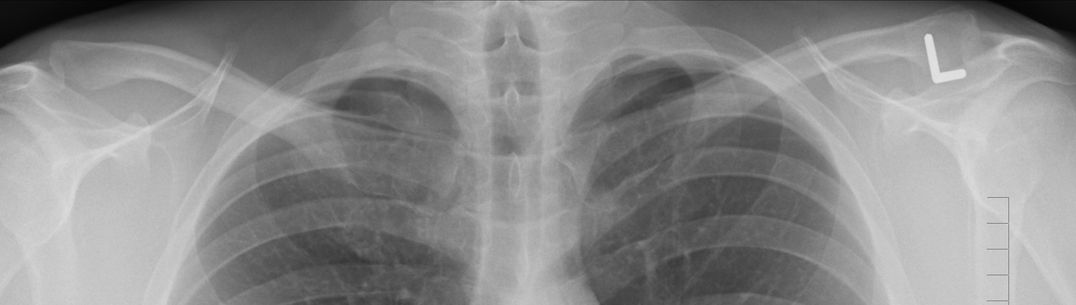

An image of a lung x-ray